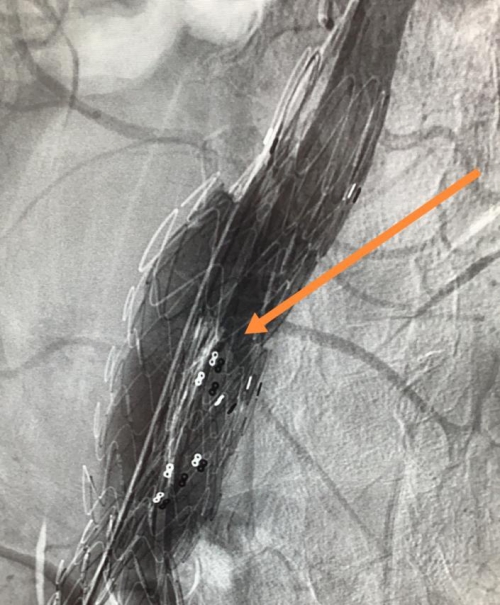

主动脉覆膜支架主体髂支衔接术中影像图

8月11日,欧阳长生为陈先生开展介入治疗,在DSA透视下反复确认支架主体释放位置后逐步释放支架系统,待左侧髂支完全释放后,再次经右侧髂动脉鞘管送入髂支分支支架,并精准于主动脉支架主体髂支衔接后稳定释放,最终实现主动脉瘤体的完全隔绝。术后造影显示瘤体完全封闭,双侧肾动脉及髂动脉血流未受到影响,手术顺利。因肾动脉血流未受影响,进一步提升了患者的生存质量。